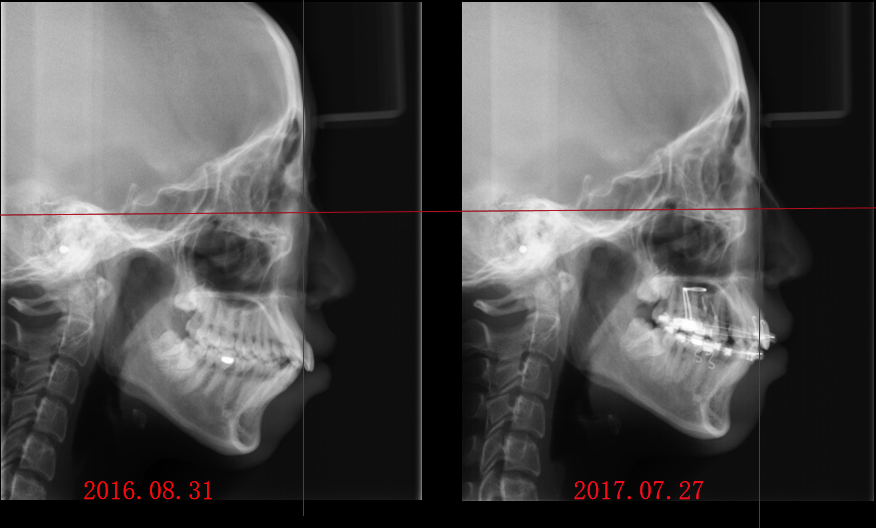

_PRE-TXNorm FMIA°47°55.0SNA°77.7°83.0SNB°70.2°80.0ANB°7.5°3.0FMA° 29.826PFH/AFH70.5°70Z Angle°50.3°77U1-FH113.0110.0IMPA°103.297.0U Lip to s’ line6.3 mm5.0L Lip to s’ line3.9 mm3.0OP-FH1215

头侧位片:

▲下颌后缩,骨性Ⅱ类

▲高角,颏部发育不足

▲上下前牙唇倾

Post-TXPRE-TXPost-TXNormFMIA°47°57.555.0SNA°77.7°76.883.0SNB°70.2°73.780.0ANB°7.5°3.13.0FMA° 29.828.026PFH/AFH70.5°65.970Z Angle°50.3°64.477U1-FH113.0103.7110.0 IMPA°103.291.197.0U Lip tos’ line6.3 mm3.25.0L Lip to s’ line3.9 mm1.03.0OP-FH1212.615